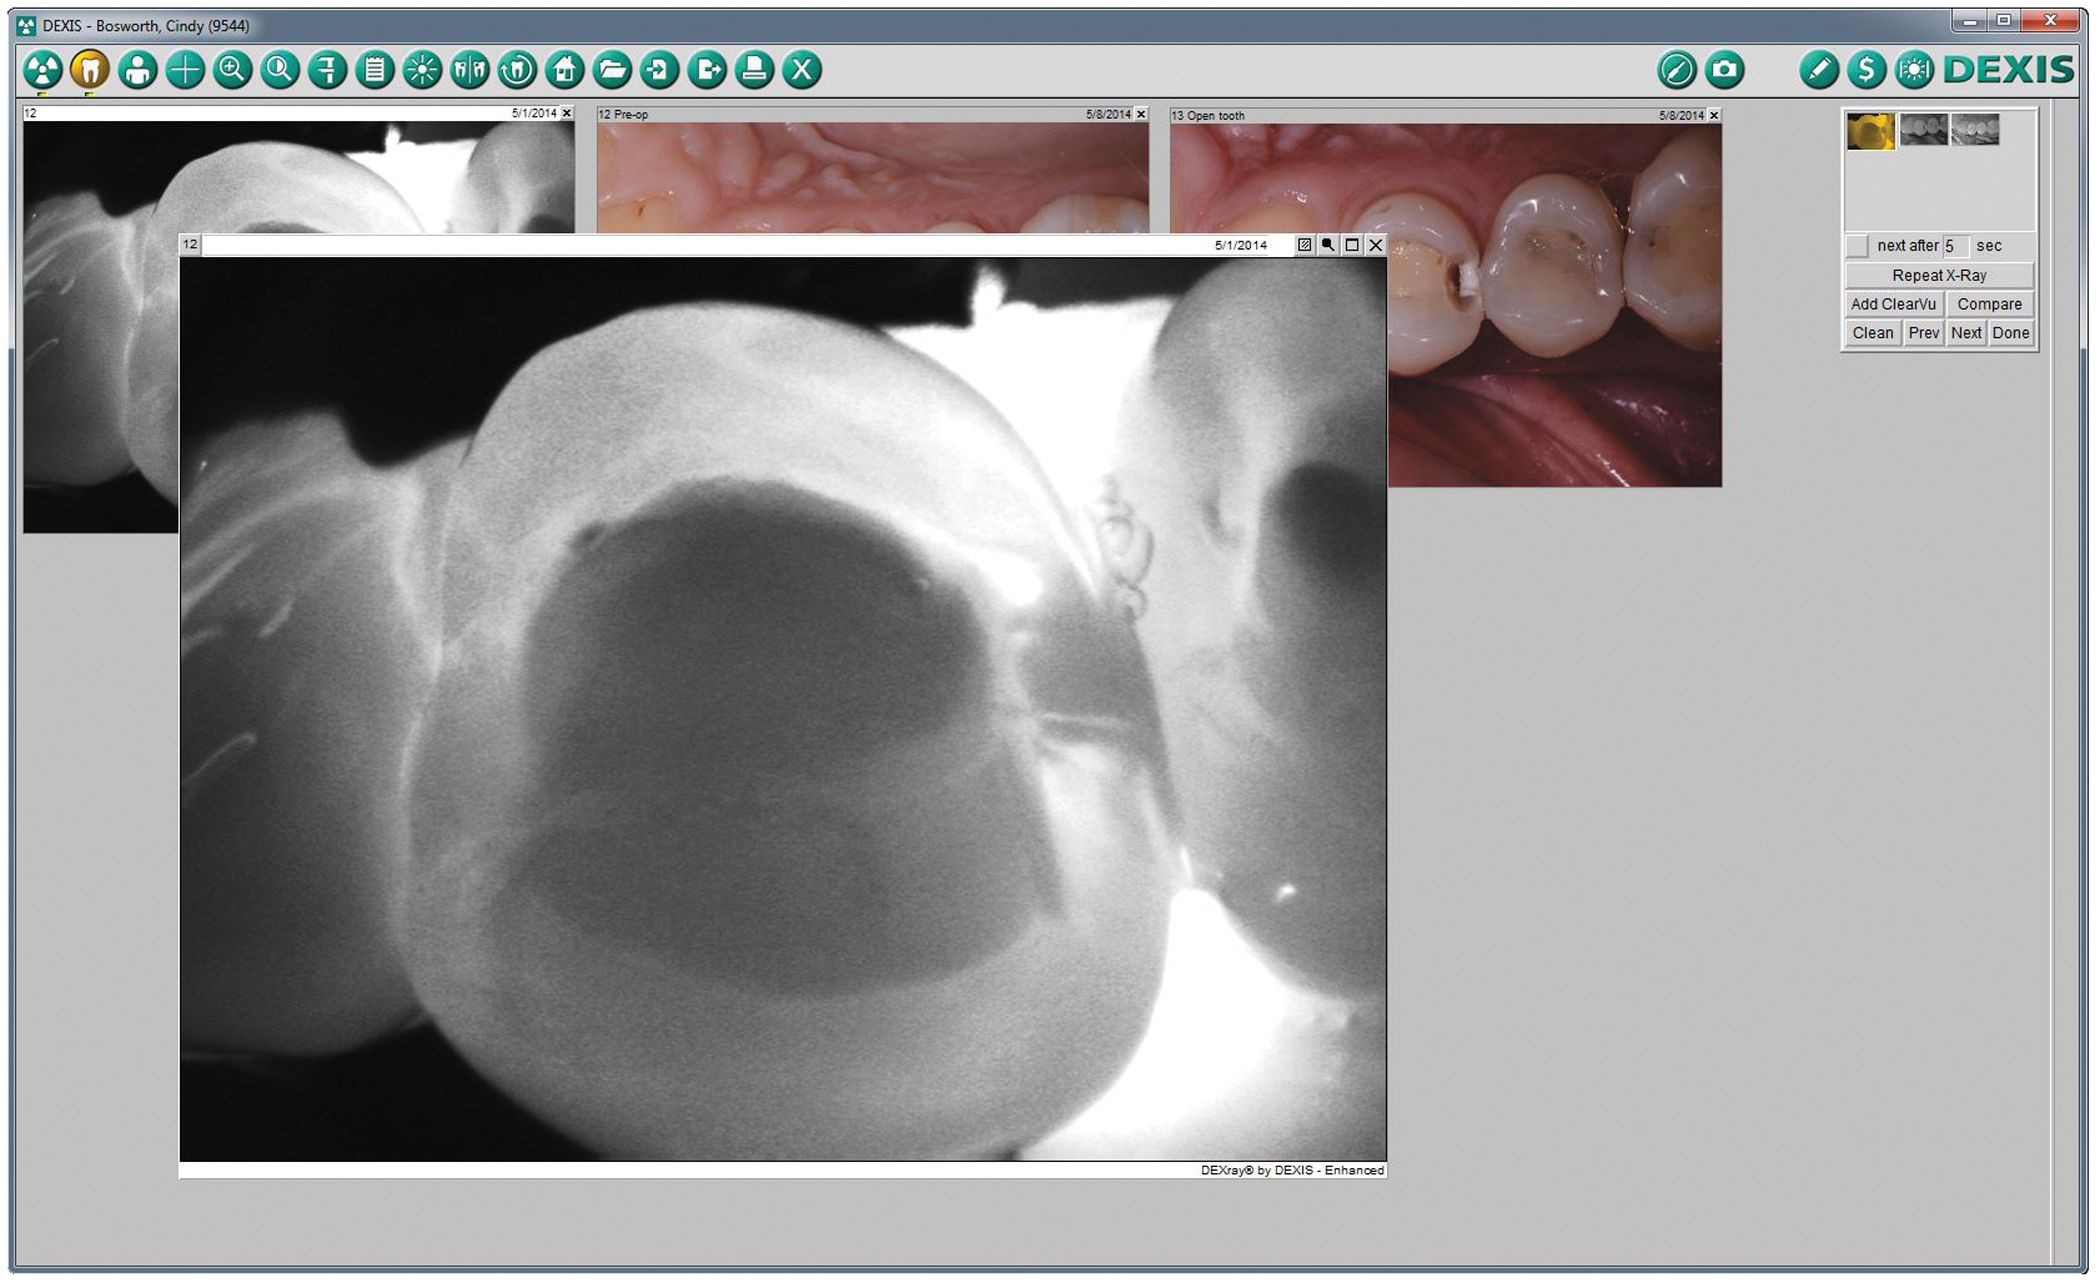

Meanwhile, images are automatically visible in the software or on my iPad with DEXIS go! The diagnosis starts here. When I enter the room, the images are ready for my review. In the software, I can see the X-rays, camera and the CariVu images side-by-side [Fig. 3].

With the tap of a finger on the iPad with DEXIS go, we easily bring up images to discuss with patients [Fig. 4]. Because CariVu images appear similar to X-rays, I explain that we are now both looking through the structure of the enamel, illuminating inside the tooth. Then, I point out that the darker area within the tooth constitutes the decay and make my treatment recommendations. This is the way we examine patients every day since I started using CariVu.

Screenshot of DEXIS CariVu.